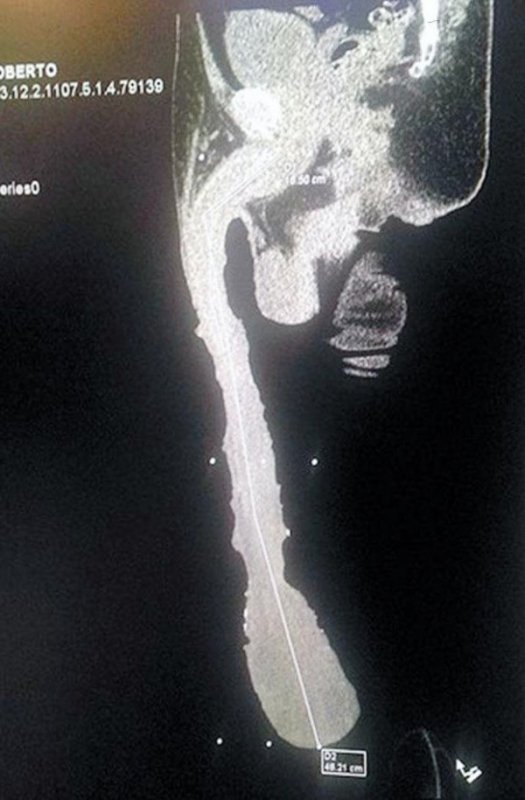

衝撃の画像。48cmのチ●コをご覧ください

gif_animation 今現在ギネスに申請中だという52歳メキシコ人男性の巨大な男性器。そのサイズ、驚愕の19インチ(48.26cm)。[3]images